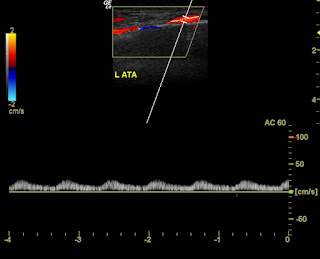

The colour Doppler ultrasound images below show changes after treatment with anticoagulants:

Note the sharp augmentation of flow on calf pressure. These images were taken four days after treatment with anticoagulants. Obviously the thrombosis of the veins has more or less resolved. the right anterior tibial vein also shows some measure of flow ( see image below):